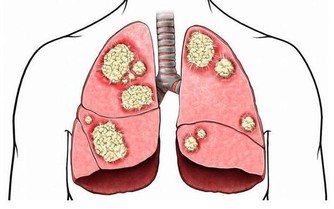

慢性腎功能衰竭,簡稱慢性腎衰,是大家經常說的“尿毒症”,屬於人類十大死因之一。我國慢性腎衰患者中,80%以上的患者發病誘因是高血壓、糖尿病和慢性腎炎。

③慢性腎炎:雖然腎炎患者相對較少,但是它一旦發病,病程進展速度更快。

此外,痛風、肥胖等也會引起慢性腎衰,同樣要注意。